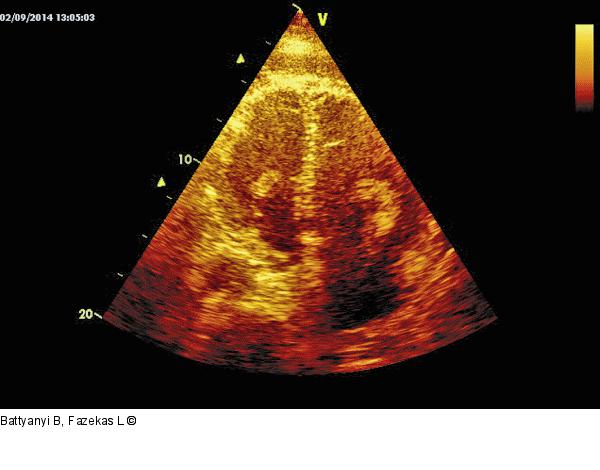

Abbildung 1: Echo Echoreiche Massen in der linken und der (mäßig dilatierten) rechten Kammer. |

Echoreiche Massen in der linken und der (mäßig dilatierten) rechten Kammer. |